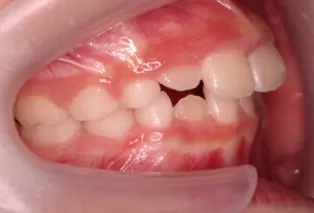

Photos intra-orales